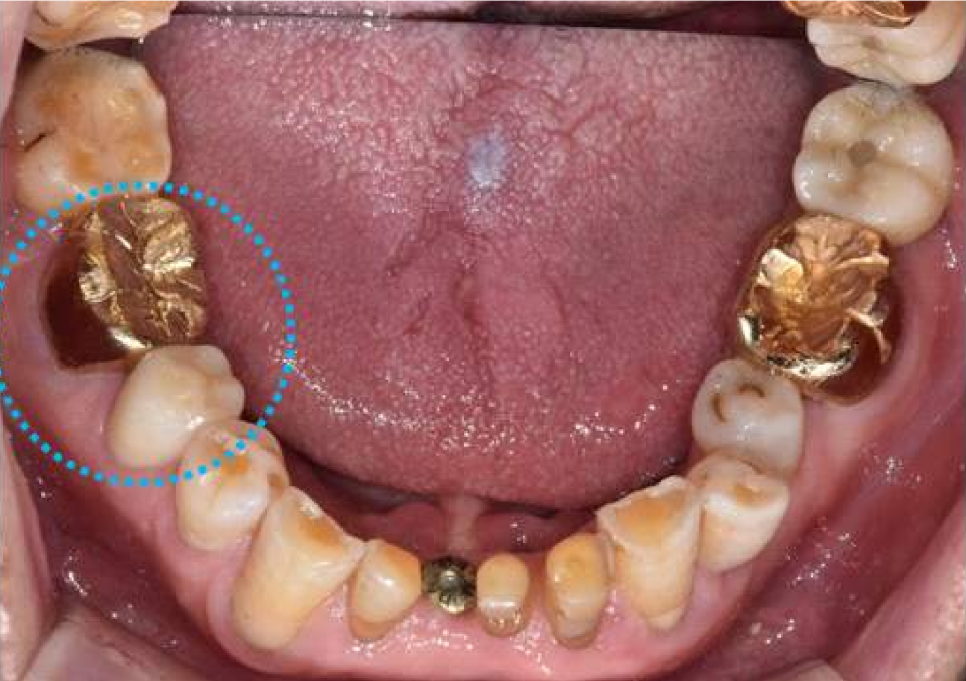

오른쪽 아래 어금니 같은 경우는

그냥 눈으로 봤을 때는 크라운 보철이 되어 있기 때문에

상태가 너무 좋아 보이지만

엑스레이상으로 보면 뿌리에 길게 신경치료 한 부분이 보이고

"뿌리 끝 염증으로 주변 뼈가 까맣게 녹고 있는 모습"이 보입니다.

오른쪽 아래 큰어금니 같은 경우에는,

이미 뼈가 많이 손상된 상태이기 때문에

뼈이식과 함께 임플란트를 같이 진행하기로 하였습니다

오른쪽 아래 작은 어금니는 염증이 작게 보이기는 하지만

큰 어금니에 비하여 심하지 않고

환자분 통증이 없기 때문에

일단 큰 어금니 먼저 치료하고 지켜보기로 하였습니다.